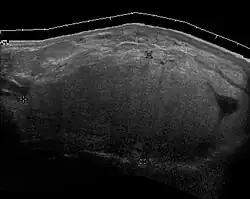

Epididymo-orchitis in a 77-year-old man. (a) Transverse sonography shows enlargement of the epididymis with hypoechogenicity noted over the testis and epididymis associated with scrotal wall thickening. (b) Color Doppler sonography showed hyperemic change of the testis and epididymis, presenting as an “inferno” vascular flow pattern.

Epididymitis and epididymo-orchitis are common causes of acute scrotal pain in adolescent boys and adults. At physical examination, they usually are palpable as tender and enlarged structures. Clinically, this disease can be differentiated from torsion of the spermatic cord by elevation of the testes above the pubic symphysis. If scrotal pain decreases, it is more likely to be due to epidiymitis rather than torsion (Prehn's sign). Most cases of epididymitis are secondary to sexually transmitted disease or retrograde bacteria infection from the urinary bladder.[6] The infection usually begins in the epididymal tail and spreads to the epididymal body and head. Approximately 20% to 40% of cases are associated with orchitis due to direct spread of infection into the testis.

At ultrasound, the findings of acute epididymitis include an enlarged hypoechoic or hyperechoic (presumably secondary to hemorrhage) epididymis [Fig. 20a]. Other signs of inflammation such as increased vascularity, reactive hydrocele, pyocele and scrotal wall thickening may also be present. Testicular involvement is confirmed by the presence of testicular enlargement and an inhomogeneous echotexture. Hypervascularity on color Doppler images [Fig. 20b] is a well-established diagnostic criterion and may be the only imaging finding of epididymo-orchitis in some men.